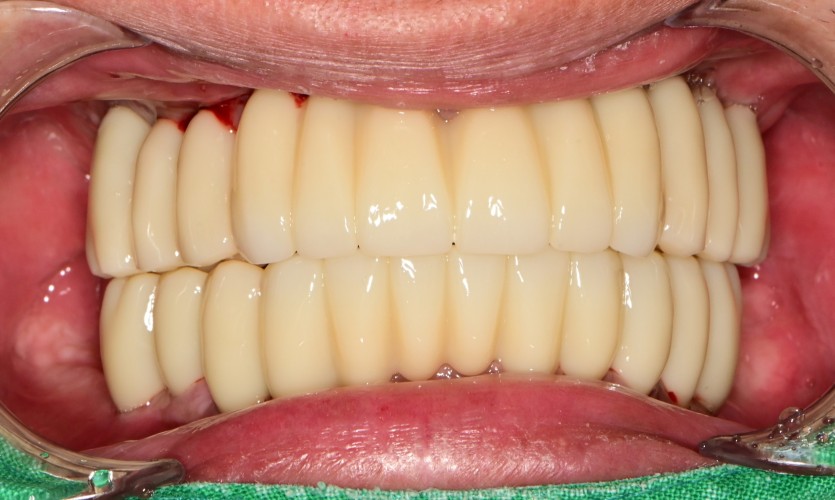

전체 임플란트 증례입니다.

18개의 임플란트로 완성하였습니다